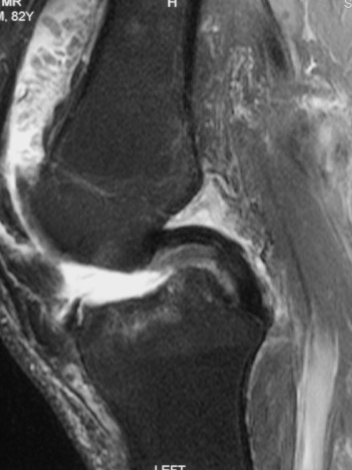

MRI

Synovial Proliferation

Soft tissue lesions same signal intensity as cartilage

Synovial chondromatosis

Synovial osteochondromatosis